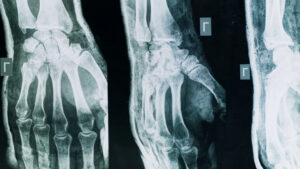

“I due cani hanno subito l’attacco di un cinghiale che ha sfondato la recinzione, un cane ferito è già stato operato dal veterinario e purtroppo ha perso una zampa, in questi giorni farà ulteriori controlli.

Situazioni che sembrano maltrattamenti a volte non lo sono, ecco perché ci tengo a verificare di persona. Il proprietario di questi animali è stato molto gentile, poteva anche cacciarmi e invece è stato molto disponibile, la catena che ha messo in questo momento ai cani è lunga più di dieci metri, è una situazione di emergenza il cinghiale che è entrato ha sfasciato tutto”.